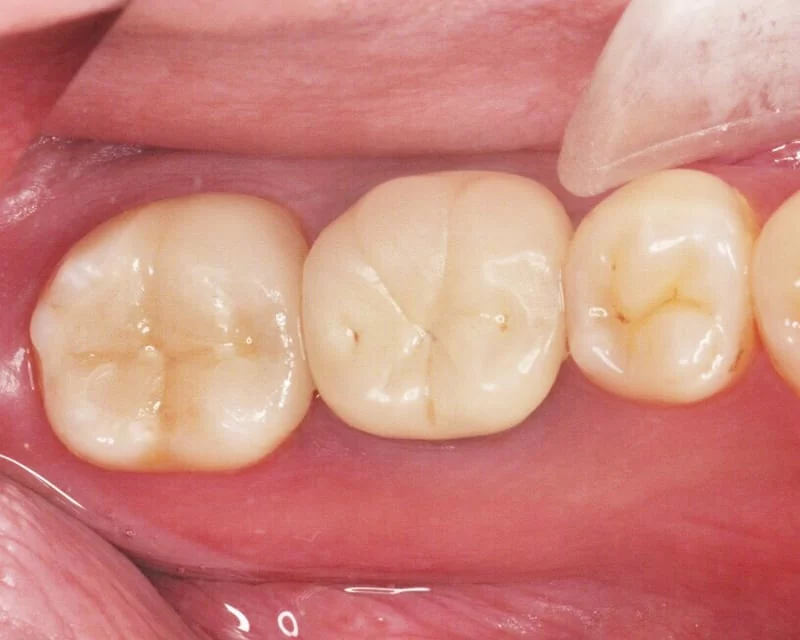

治療後